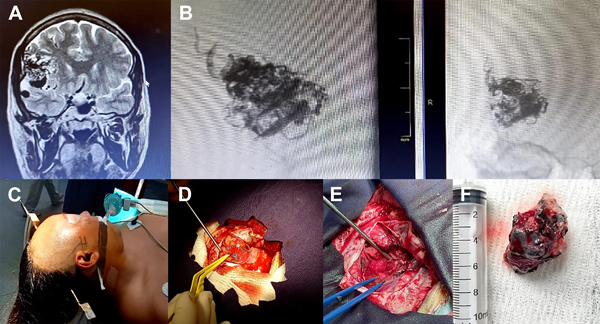

Figura 3: A: MAV Fronto-silviana derecha Grado IIIA ; B: Angiografía y pack de embolización (Gentileza Dres. Matías Quaglia y la Dra. Danaes Prieto quienes realizaron la embolización prequirúrgica); C: abordaje y posicionamiento; D: exposición opercular con MAV en Valle Silviano ; E: Lodge quirúrgica con la resección completa de la MAV y preservación de la vasculatura normal; F: MAV resecada